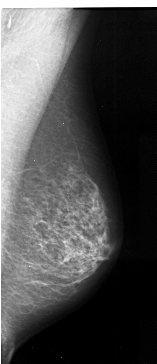

A_1032_1.LEFT_CC

LEFT_CC LINES 4171 PIXELS_PER_LINE 2146 BITS_PER_PIXEL 16 RESOLUTION 42 OVERLAY